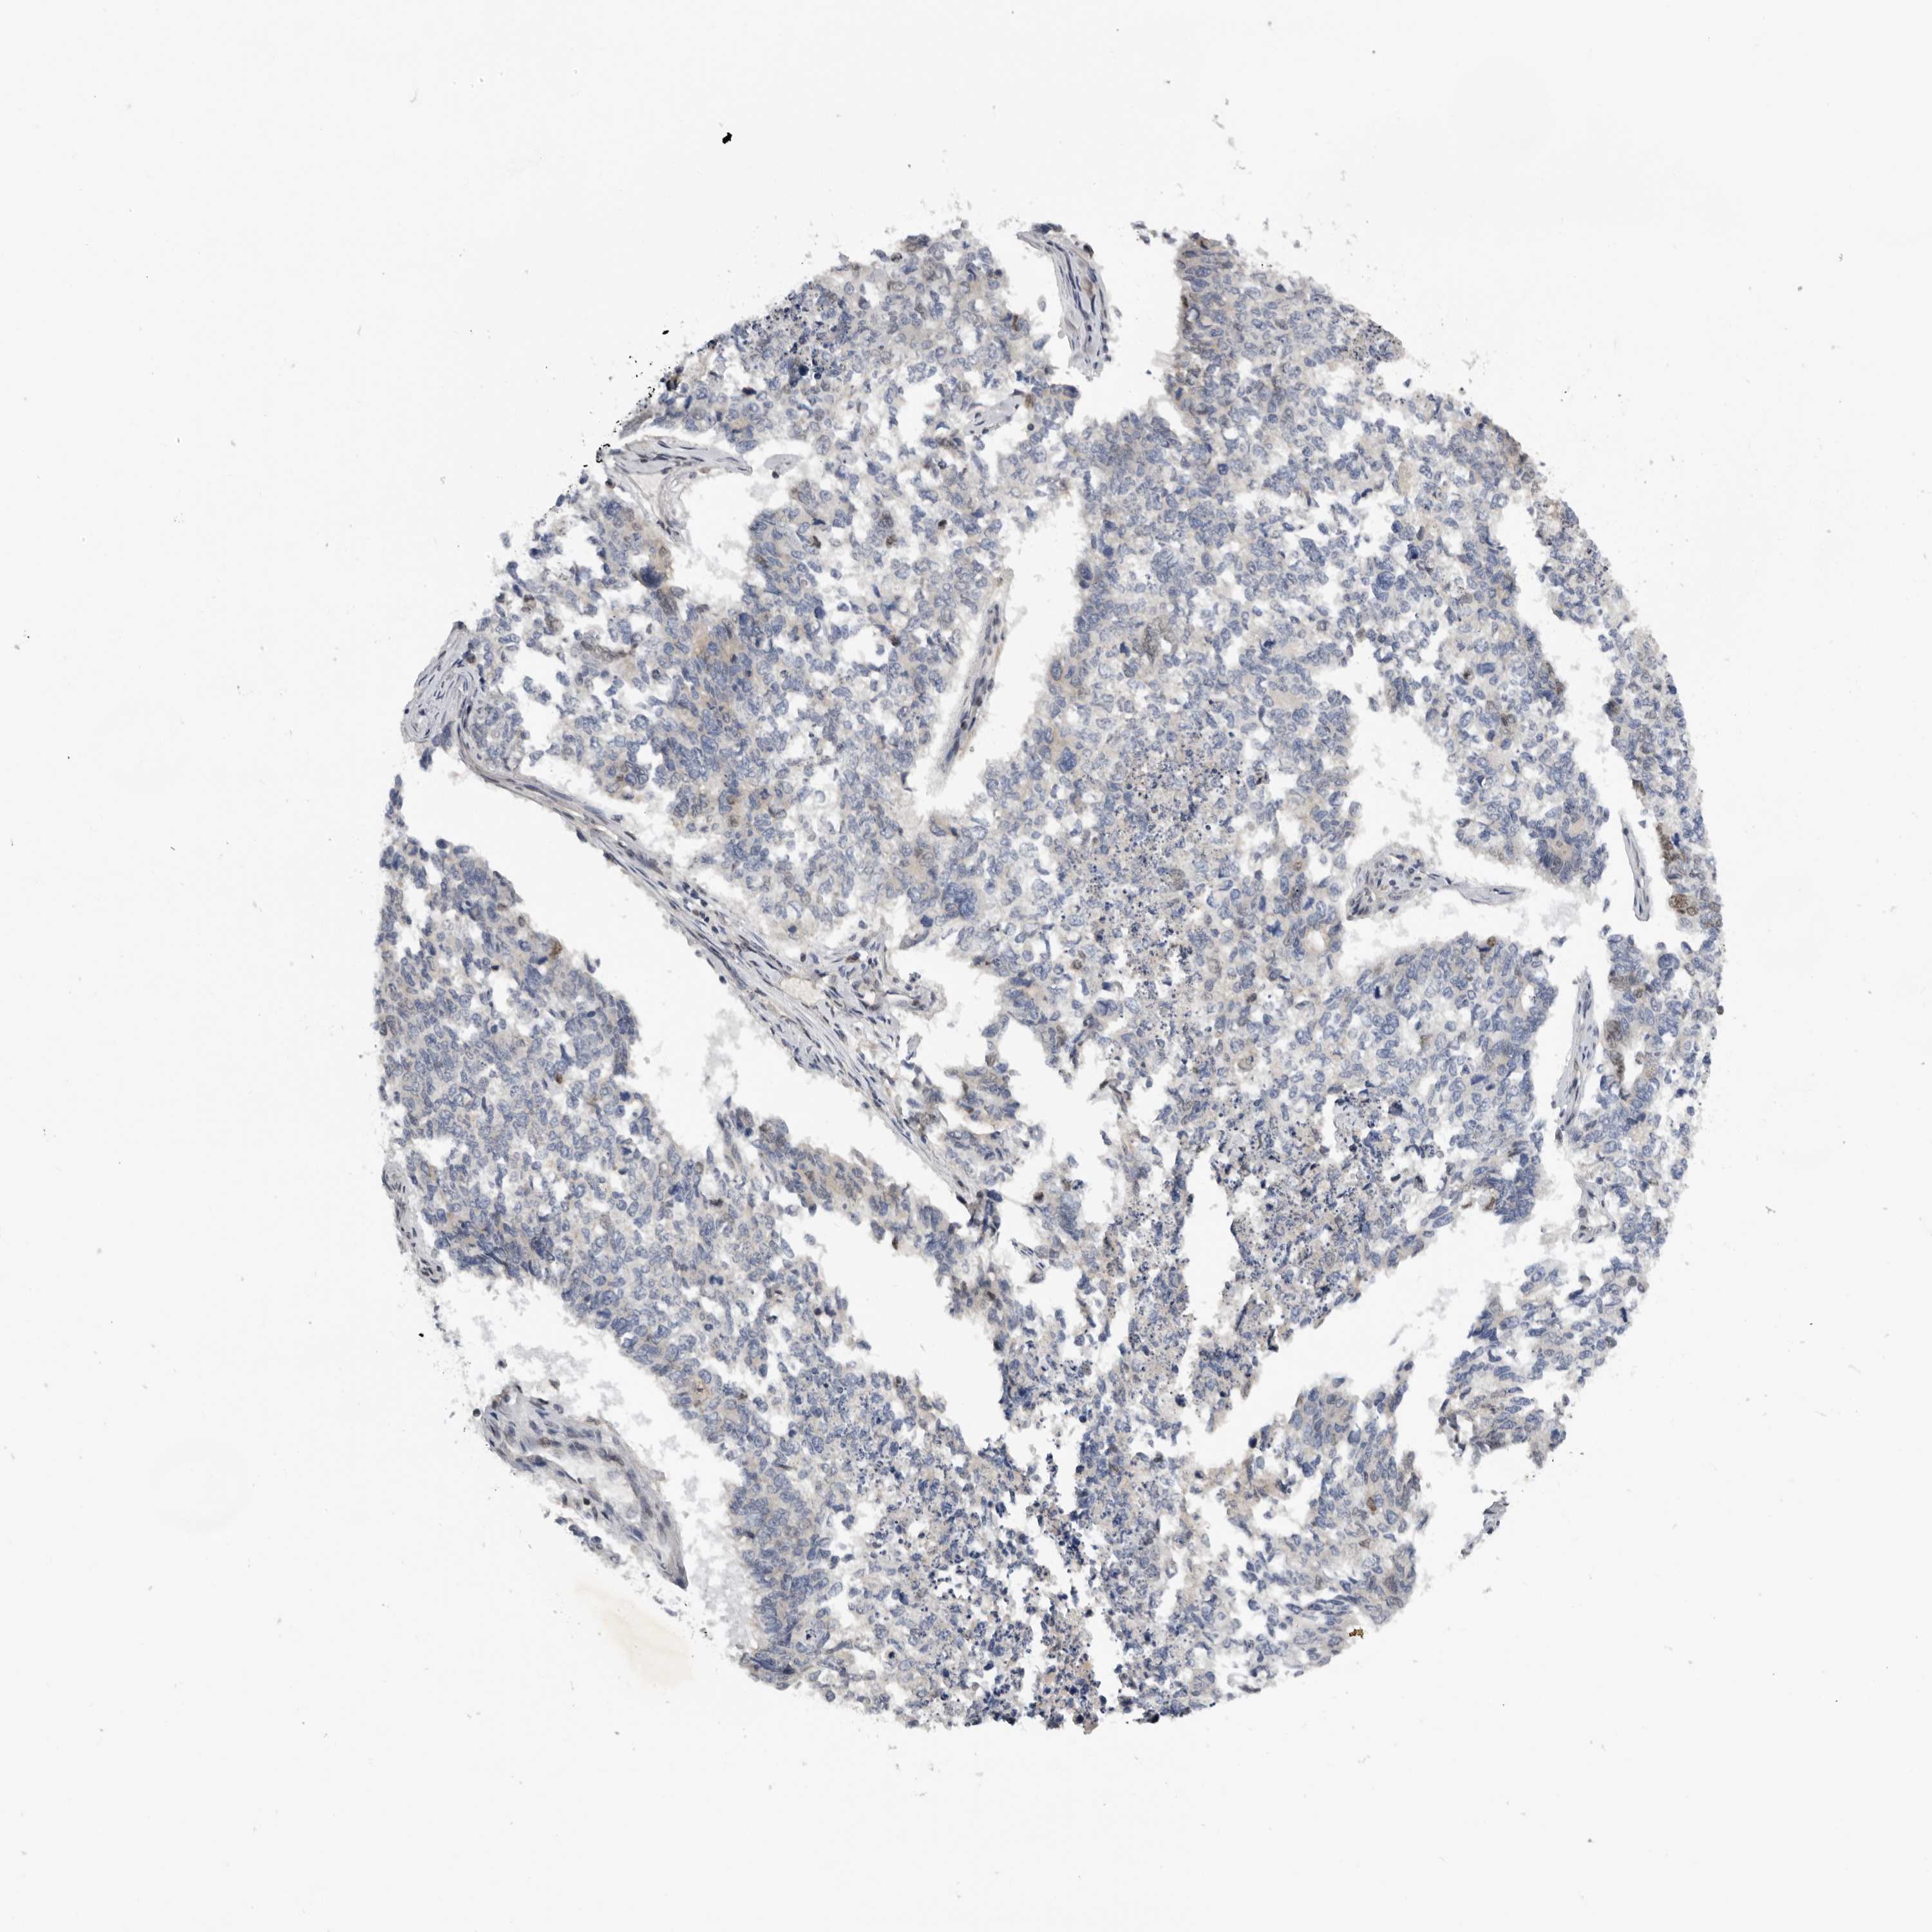

CERVICAL CANCER - Protein expressioni

A mouse-over function shows sample information and annotation data. Click on an image to view it in a full screen mode. Samples can be filtered based on level of antibody staining by selecting one or several of the following categories: high, medium, low and not detected. The assay and annotation is described here.

Note that samples used for immunohistochemistry by the Human Protein Atlas do not correspond to samples in the TCGA dataset.

Antibody stainingi

Antibody staining in the annotated cell types in the current human tissue is reported as not detected, low, medium, or high, based on conventional immunohistochemistry profiling in selected tissues. This score is based on the combination of the staining intensity and fraction of stained cells.

Each image is clickable and will lead to virtual microscopy that enables deeper exploration of all samples and also displays staining intensity scores, fraction scores and subcellular localization as well as patient and tissue information for each sample.

Antibody HPA023081

Antibody HPA023103

Antibody HPA024795